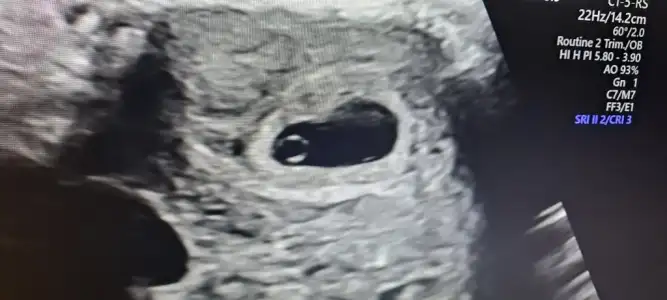

Kızlar devlete gittim kesem içinde bebeğim gözüktü kalp atışına 10 gün sonra gel dedi ama ben bugün öğlen sonu özele de gidicem artık oraya gideceğim için başlangıcı yaptircam fasulye gibi kesesi ya🥰

Oy maşallah ya benimki neden bu kadar net değil ya 🧿🧿🧿🧿 maşallah maşallah 🙈🙈🙈 acaba bebişi görmedi diye mi 🙈🙈

Maşallah gözün aydın canım darısı başıma benden de bugün kan aldılar artışa bakılacak sanırım ona göre bakarız keseye dedi sende sadece kesemi gözuktü bebekte varmıydı